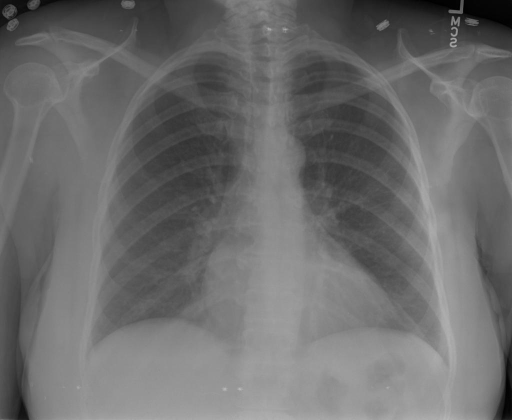

# 本文贡献  - 借助ChatGPT以及公开的数据集,我们构造了一个`X光影像-诊断报告`对的医学多模态数据集; # 数据集 - [MIMIC-CXR](https://physionet.org/content/mimic-cxr-jpg/2.0.0/)是一个公开可用的胸部X光片数据集,包括377,110张图像和227,827个相关报告。 - [OpenI](https://openi.nlm.nih.gov/faq#collection)是一个来自印第安纳大学医院的胸部X光片数据集,包括6,459张图像和3,955个报告。 在上述工作中,报告信息都为非结构化的,不利于科学研究。为了生成合理的医学报告,我们对两个数据集进行了预处理,并最终得到了可以用于训练的**英文报告**。除此之外,为了更好的支持中文社区发展,借助ChatGPT的能力,我们将英文报告进行了中文翻译,并最终形成了可用于训练的数据集。 |数据集|数量|下载链接| |:-|:-|:-| |MIMIC-CXR-zh|-|-| |OpenI-zh|6,423|[诊疗报告](./data/Xray/openi-zh.json) 、[X光影像](https://pan.baidu.com/s/13GBsDMKf6xBZBSHpoWH_EA?pwd=k9sh)| # 快速上手 1. 安装环境 ```bash # 安装依赖 pip install -r requirements.txt # 国内换源安装依赖 pip install -i https://mirrors.aliyun.com/pypi/simple/ -r requirements.txt ``` 此时默认会安装`deepspeed`库(支持`sat`库训练),此库对于模型推理并非必要,同时部分`Windows`环境安装此库时会遇到问题。 如果想绕过`deepspeed`安装,我们可以将命令改为: ```bash # 安装依赖 pip install -i https://mirrors.aliyun.com/pypi/simple/ -r requirements_wo_ds.txt # 安装SwissArmyTransformer pip install -i https://mirrors.aliyun.com/pypi/simple/ --no-deps "SwissArmyTransformer>=0.3.6" ``` 2. 模型推理 CLI推理: ```python python cli_demo.py --from_pretrained checkpoints/finetune-XrayGLM-05-25-01-04 --prompt_zh '详细描述这张胸部X光片的诊断结果' ``` 更多[参数](https://github.com/WangRongsheng/XrayGLM/blob/main/cli_demo.py#L16) # 效果展示 诊断: |X光影像|诊疗报告(医生)|XrayGLM| |:-|:-|:-| ||根据X射线图像,心脏大小正常,肺部看起来很清晰。已经排除了肺炎、积液、水肿、气胸、腺病、结节或肿块的存在。该发现表明一切正常。换句话说,总体印象是胸部正常。|X光片显示,心脏大小正常。肺部没有气胸或胸腔积液的证据。骨骼结构看起来没有任何异常。总的来说,X光片表明没有发现急性心肺疾病的迹象。| ||X光图片显示没有扭曲的区域、可疑的骨质不透明度或胸腺积液。心脏大小轻微增大,但非常稳定。此外,没有气胸的证据,肺野也正常。总体来说,X光片显示没有急性心脏异常,但要注意轻微的心脏扩大。|X光片显示,心脏大小正常。肺部和纵隔轮廓清晰,没有气胸或胸腔积液的证据。骨骼结构完整,没有任何急性异常。| ||心影形态在正常范围内。没有急性骨质异常。有可能出现没有明显的吸水或肺实质状况的线索。没有大面积积液或气胸。有可能怀疑其有误吸或肺实质问题。为了确诊和治疗,可能需要进行适当的影像学随访。|心脏大小正常,肺部和纵隔轮廓清晰。没有急性异常或活动受限的证据。没有任何明显的气胸、胸腔积液或肺不张的迹象。此外,也没有发现任何局灶性骨质异常或其他急性疾病。| 多轮对话: |X光影像|诊疗报告(医生)| |:-|:-| ||右侧主动脉突出观察到。心脏大小正常。胸部未发现明显的肺气肿、胸膜积液或可疑的肺部病变。报告指出已知右侧主动脉情况正常。| ```bash >> X光影像路径:./data/Xray/861_1.png >> 用户:这是一张什么图? >> XrayGLM:这张图片显示的是一张肺部检查的X光片。 >> 用户:请描述这张胸部X光片的诊断结果 >> XrayGLM:心脏大小正常,肺部清晰。没有急性心肺疾病的证据。 >> 用户:是否存在肺气肿? >> XrayGLM:没有肺气肿。心脏大小正常,肺部清晰。没有发现急性心肺疾病的证据。 >> 用户:平时饮食该注意什么? >> XrayGLM:饮食应该健康,均衡。建议增加蛋白质的摄入量,因为蛋白质有助于维持肌肉和骨骼的健康。多食用蔬菜、水果、全谷物以及健康的脂肪来源如橄榄油、鱼类等可以帮助获得足够的维生素和矿物质。此外,避免过度饮酒或吸烟,这些习惯可能会对心脏健康产生负面影响。 ``` # 项目致谢 1. [VisualGLM-6B](https://github.com/THUDM/VisualGLM-6B)为我们提供了基础的代码参考和实现; 2. [MiniGPT-4](https://github.com/Vision-CAIR/MiniGPT-4)为我们这个项目提供了研发思路; 3. ChatGPT生成了高质量的中文版X光检查报告以支持XrayGLM训练; 4. [gpt_academic](https://github.com/binary-husky/gpt_academic)为文档翻译提供了多线程加速; 5. [MedCLIP](https://github.com/RyanWangZf/MedCLIP) 、[BLIP2](https://huggingface.co/docs/transformers/main/model_doc/blip-2) 、[XrayGPT](https://github.com/mbzuai-oryx/XrayGPT) 等工作也有重大的参考意义;  这项工作由[澳门理工大学应用科学学院](https://www.mpu.edu.mo/esca/zh/index.php)硕士生[王荣胜](https://github.com/WangRongsheng) 、[段耀菲](https://github.com/IsBaSO4) 、[李俊蓉](https://github.com/lijunrong0815)完成,指导老师为檀韬副教授、[彭祥佑](http://www.patrickpang.net/)老师。 *特别鸣谢:[USTC-PhD Yongle Luo](https://github.com/kaixindelele) 提供了有3000美金的OpenAI账号,帮助我们完成大量的X光报告翻译工作 # 免责声明 本项目相关资源仅供学术研究之用,严禁用于商业用途。使用涉及第三方代码的部分时,请严格遵循相应的开源协议。模型生成的内容受模型计算、随机性和量化精度损失等因素影响,本项目无法对其准确性作出保证。即使本项目模型输出符合医学事实,也不能被用作实际医学诊断的依据。对于模型输出的任何内容,本项目不承担任何法律责任,亦不对因使用相关资源和输出结果而可能产生的任何损失承担责任。 # 项目引用 如果你使用了本项目的模型,数据或者代码,请声明引用: ```bash @misc{wang2023XrayGLM, title={XrayGLM: The first Chinese Medical Multimodal Model that Chest Radiographs Summarization}, author={Rongsheng Wang, Yaofei Duan, Junrong Li, Patrick Pang and Tao Tan}, year={2023}, publisher = {GitHub}, journal = {GitHub repository}, howpublished = {\url{https://github.com/WangRongsheng/XrayGLM}}, } ``` # 使用许可 此存储库遵循[CC BY-NC-SA](https://creativecommons.org/licenses/by-nc-sa/4.0/) ,请参阅许可条款。